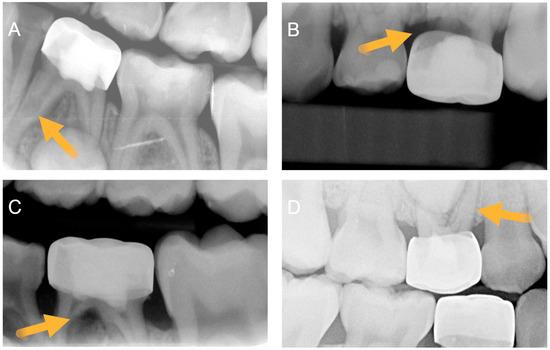

Figure 1